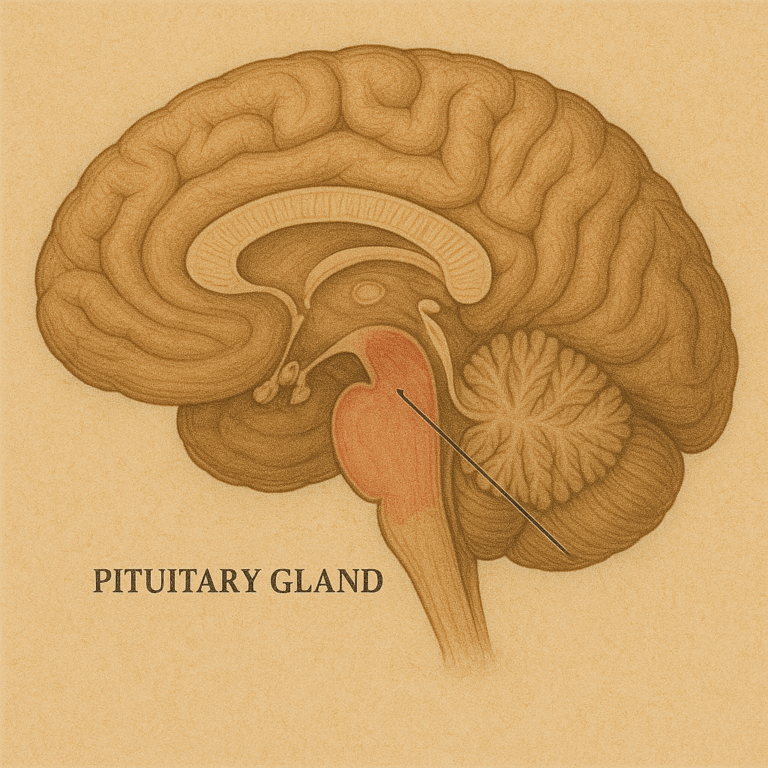

En el interior del cráneo, justo en la base del cerebro y…